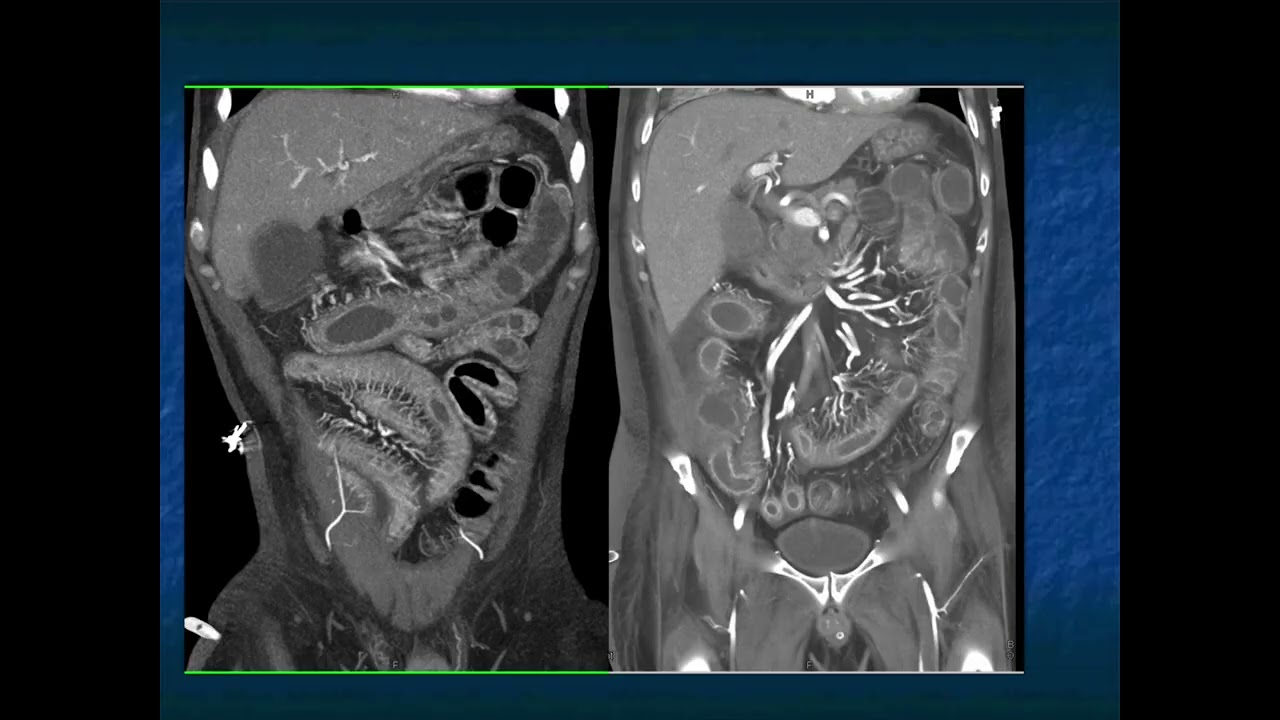

Abdominal Pain in the ER: GI Pathology - Part 2

CTisus.com is an informational and educational radiological resource dedicated to CT scanning. Founded by Elliot K. Fishman, M.D. The website provides the latest information regarding radiology technology and 3D imaging. It features a library of content, including lectures and case studies, as well as medical illustrations and other radiology resources.